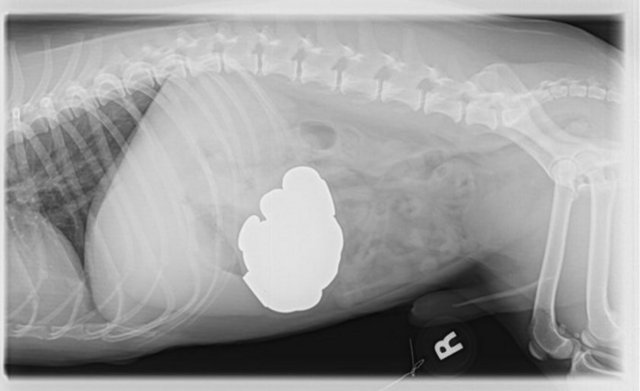

"Özellikle havaalanlarındaki girişlerde iki tür cihazı da görebiliriz. Eşyaların geçirildiği X-Ray cihazında X ışınları kullanılarak görüntüleme yapılır. Çantaların içinde ne olduğu X ışınları ile görüntülenir. Burada uygulanan X ışınlarının eşyalara bir zararı yoktur, birikmez, eşyalarda radyasyon kirliliği yapmaz. Bu cihazların çevresi X ışınlarının insanlara zarar vermemesi için kurşun paravanlarla kaplıdır."